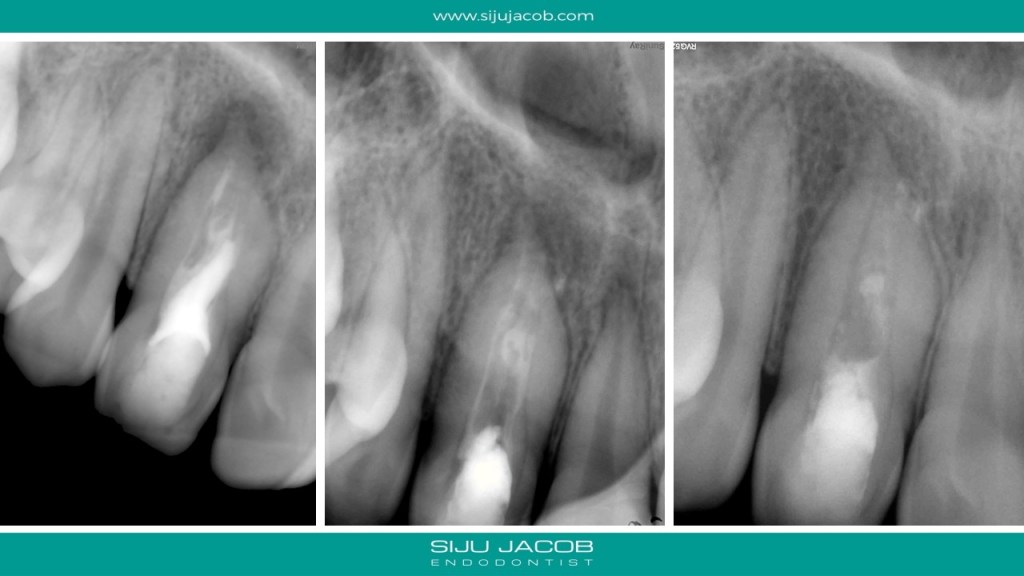

I initially thought of treating only the necrotic dens in this case because the tooth responded to heat and cold indicating that the apical lesion was probably from the dens. But, after the initial visits, the patient had persistent pain. So, I opened up both the canals, one of which was very hyperemic. I put this tooth on calcium hydroxide for 12 months and Obturated after the lesion healed. Placed Fiber-posts to strengthen the tooth. No crown for now.